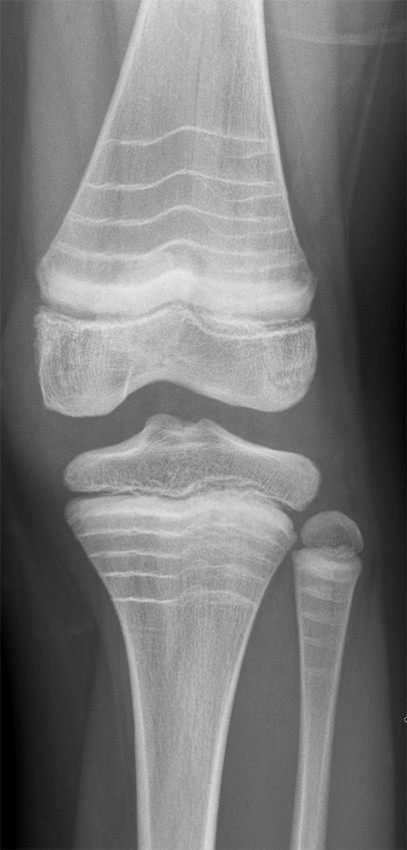

This X-ray shows the knee of a teenage boy with multiple, transverse, sclerotic (white) bands in the tibial and femoral metaphyses. The patient has similar bands in several other joints. He has been diagnosed with osteogenesis imperfecta type 1 and has been receiving treatment with intravenous zoledronic acid (bisphosphonate) for five years. Each of the transverse bands corresponds to a treatment cycle/injection of bisphosphonate. More frequent injections result in shorter band intervals. The bands are most common in the metaphyses, but can also occur in the epiphyses and apophyses. The sclerotic bands are the result of increased bone mineralisation (1) and are an indirect response to inhibition of osteoclast activity as a result of treatment. In 2007, it was proposed that the bands should be called 'zebra lines' (2).

Osteogenesis imperfecta (OI) is a congenital disease of collagen fibres that affects the skeleton in particular, but also the connective tissues. There are five subtypes of osteogenesis imperfecta, with different genetic causes and severities. Type 1 is the mildest and most common form. All types are characterised by abnormal collagen fibre synthesis, with changes either to the structure of collagen or to the number of fibres produced. This results in weakening of the skeleton, reducing its ability to withstand mechanical stress and thereby increasing the risk of bone pain/fractures and skeletal deformity (3). There is no curative treatment available for the disorder. However, multidisciplinary treatment aims to reduce the risk of fractures and complications of fractures, and to help patients function as well as possible.

The need for drug treatment with intravenous bisphosphonate is assessed on the basis of fracture history and severity. Bisphosphonate increases the mineralisation of bone tissue, but does not affect the collagen abnormalities per se. Zoledronic acid is administered every six months from the age of two and usually until the child is fully grown, but treatment duration is decided on an individual basis. Zoledronic acid is not approved for use below the age of two years, and younger children are usually treated with monthly pamidronate infusions.